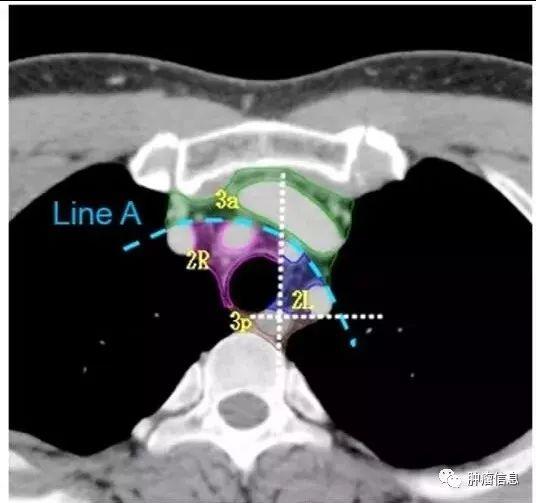

2R:右侧上气管旁,自胸骨柄上界至无名静脉足侧与气管交汇处,自气管右侧至气管左侧缘。2L:左侧上气管旁,自胸骨柄上缘至主动脉弓上缘,气管左侧缘以左。气管左侧缘是2R和2L的分界线。

第3组淋巴结

第3组淋巴结分为3a和3p:3a:前部的血管前淋巴结上界:胸膜顶下界:隆突水平前界:胸骨后后界:上腔静脉前缘3p:后部的气管后淋巴结上界:胸膜顶下界:隆突水平